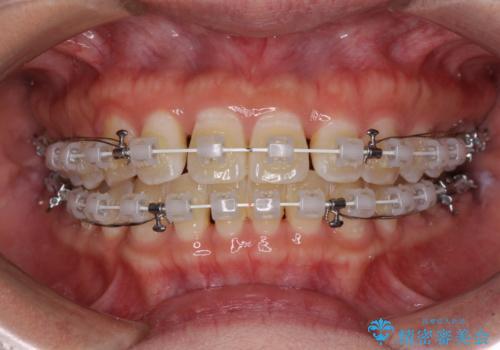

- 矯正装置

- 審美装置

正中がなかなか合わずに、2年近くの治療期間を要しました。